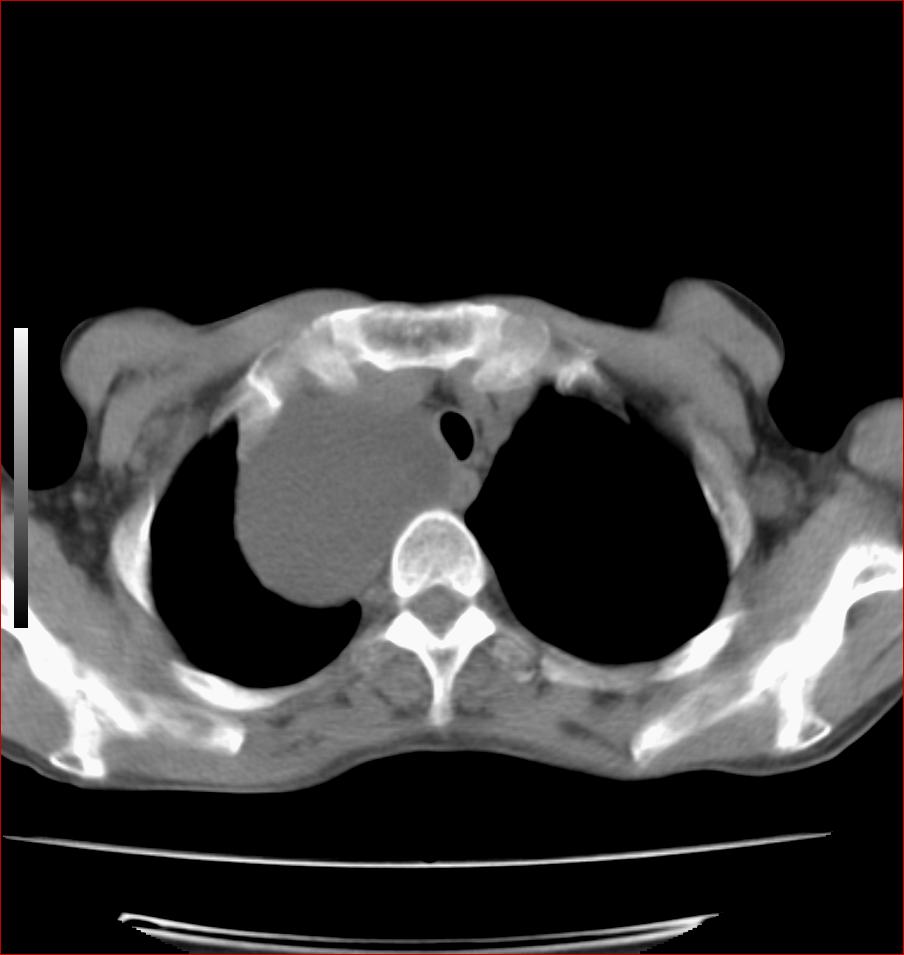

标题: CT17110:F56Y,纵隔囊肿;胸腺?淋巴?请各位老师看看 [打印本页]

女性患者 56 咽痛伴声嘶10+天入院。

病变紧贴气管右壁,两者相互压迫,考虑支气管囊肿!

见相互挤压征,考虑气管囊肿,建议ct增强扫描

病变紧贴气管右壁,两者相互压迫,考虑支气管囊肿!  建议强化